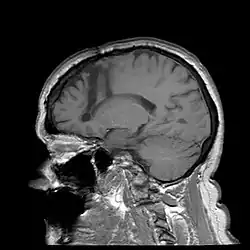

One of the most notable treatments for the brain occurring in the 20th century was the lobotomy, which was invented in 1935 by Portuguese Neurologist Egas Moniz.[28] The lobotomy was a surgical procedure performed on the brain that targeted the frontal lobe, which is the part of the human brain that controls emotional response. The reason the lobotomy targeted this particular lobe was to reduce stress and other negative emotions to cure disabilities.[29]

Additionally, advancements in neurosurgery have enabled the treatment of certain neurological conditions associated with disabilities. Deep brain stimulation (DBS), for instance, has been increasingly used to manage symptoms of movement disorders like Parkinson's disease and dystonia. By implanting electrodes deep into specific brain regions and delivering controlled electrical impulses, DBS can help regulate abnormal neural activity, thereby improving motor function and reducing disability-related impairments.[45]